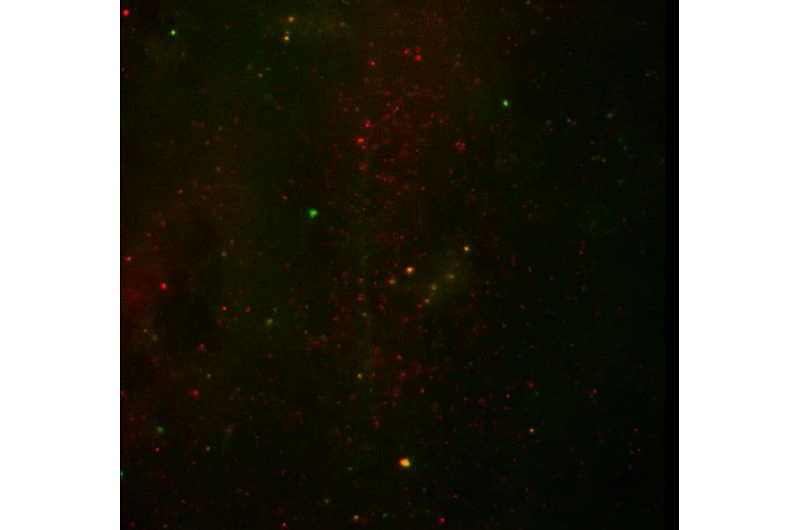

Movie of nanoparticles moving through mucus. Credit: Schneider et al. Sci. Adv. 2017;3:e1601556